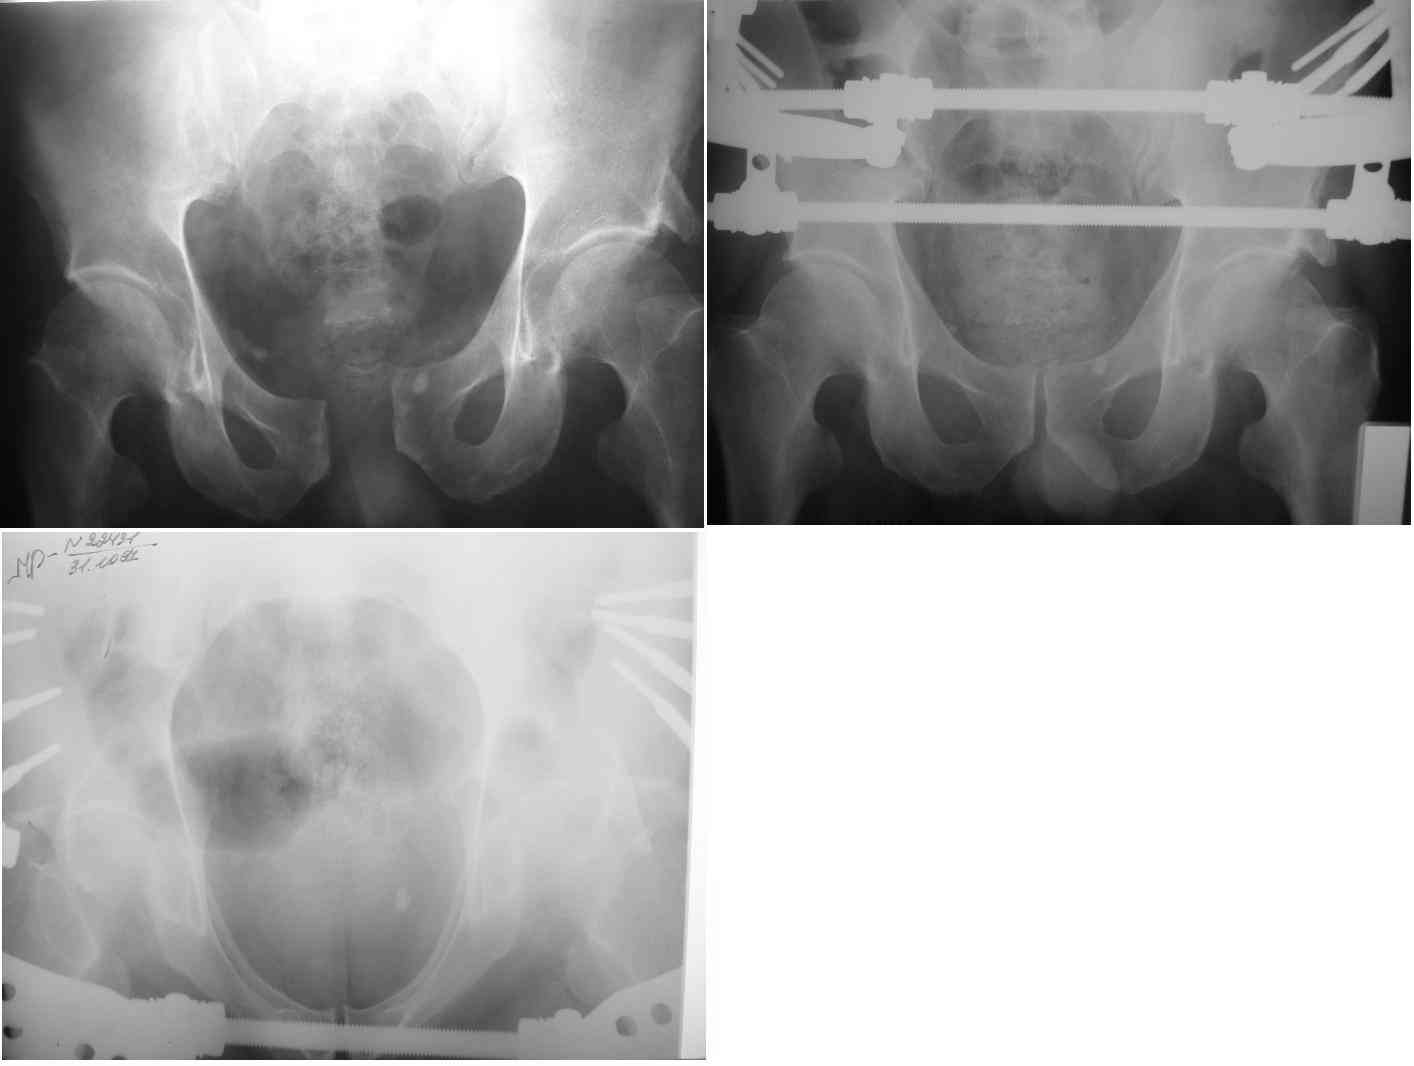

извините за опоздание , вот фотографии

Репозиция действительно очень неплохая, но чтобы уменьшить риск развития поздней нестабильности, в такой ситуации лучше выполнить синтез лонного сочленения пластиной и оставить аппарат месяца на 2.

В представленном случае повреждение несомненно ротационное и реальный диастаз как раз около пограничных 2,5 см, репозиция идеальная, достигнута в первые дни после травмы. Я бы ограничился 3 мес фиксации в аппарате с ограничением нагрузки первый месяц, и функциональными снимками в 6 -8 недель.

В представленном случае повреждение несомненно ротационное и реальный диастаз как раз около пограничных 2,5 см, репозиция идеальная,

достигнута в первые дни после травмы. Я бы ограничился 3 мес фиксации в

аппарате с ограничением нагрузки первый месяц, и функциональными снимками в 6 -8 недель.

Андрею Миронову: Коллега, лучшее враг хорошего! Если пациент хорошо переносит аппарат, ходит свободно, т.е. фиксация стабильна, оставьте как есть. Но, вообще, аппарат при разрывах тазового кольца применяют как экстренную меру для борьбы с шоком, и после стабилизации общего состояния переходят на внутреннюю фиксацию..., конечно, не через 6-8 недель.